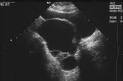

Tumore de ovarios

Se consideran las neoplasias del aparato genital más frecuentes durante la infancia, aunque represetan solo 1% de todos los tumores de ovarios diagnosticados en todas las edades. Tradiacionalmente se pensaba que toda neoplasia ovárica diagnosticada durante la niñez debía extrirpace siempre: pero hoy en día, gracias a la identicación de marcadores tumorales sérios y a los avances en técnicas de imagenologías, ha surgido un enfoque mucho más racional y conservador en la atencion de estas tumoraciones.

Quistes ovaricos funcionales

Constituyen de 20 a 50 % del total de los tumores ováricos. No son verdaderas neoplasias, sino que se concideran como variantes de un proceso fisiologico normal. Estan los foliculares, luteínicos o simples, que se han considerado como la segunda causa de tumores ováricos a estas edades. Estas neoplasias no constituyen un grave peligro para las pacientes y con frecuencia son asintomáticas, además por lo general regresan de manera espontanea.